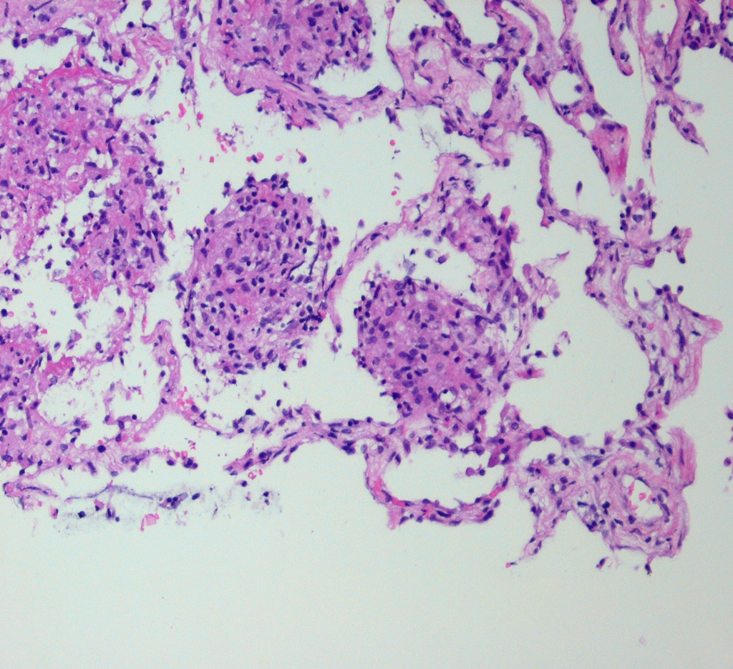

What does this show?

Granulomatous inflammation